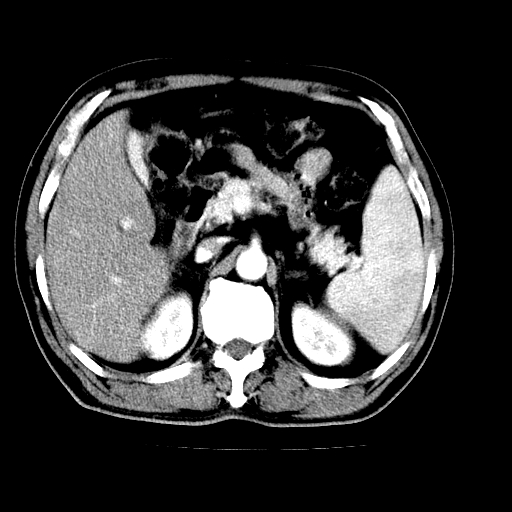

男,66岁,上腹部不适、黄染一周。彩超示:肝左叶占位,肝内胆管扩张,胆总管扩张,胆总管占位?

肝左叶不规则软组织肿块影,边缘不规整邻近肝实质受累分界不清;肝内胆管(左叶)明显扩张成“软藤状”,诊断:肝左叶胆管细胞癌。

肝左叶占位性病变,并胆管扩张,符合胆管细胞癌ct表现,门脉左支受累,左肾囊肿。窗宽太窄了,其他的看不清

左叶胆管细胞癌累及胆总管,门脉左支受侵,慢性胆囊炎胆结石,左肾小囊肿

肝左叶不规则软组织肿块影,边缘不规整邻近肝实质受累分界不清;肝内胆管(左叶)明显扩张成“软藤状”,诊断:肝左叶胆管细胞癌。胆囊钙乳症。